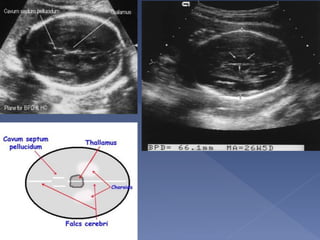

Landmarks :

 Midline Falx

cerebri

 Cavum septum

pellucidum

 Thalami

symmetrically

positioned on

either side of the

falx

 Lateral ventricle

 The diameter between the 2 sides of the

head

 This is measured after 13 weeks.

 Dating using the BPD should be done as

early as is feasible.

 Different babies of the same weight can

have different head size, therefore dating in

the later part of pregnancy is generally

considered unreliable

 The BPD remains the standard against

which other parameters of gestational age

assessment are compared

 A wrong measurement plane can produce

errors up to 20mm !

 The measurement is taken from the

outer edge of the near cranium to the

inner edge of the far cranium.

 a middle-to-middle measurement is

also acceptable.

 The BPD can be smaller (and sometimes

much smaller than is expected) in

fetuses with flatter heads(check the

head circumference)

Landmarks:

 Same as BPD

 On the outer

margin of the bony

skull

 Independent of

skull shape

 More indicative of

gestational age